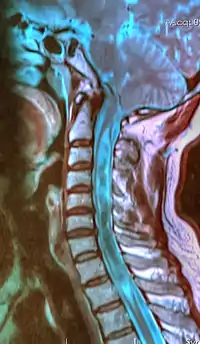

A sagittal FLAIR MRI scan, from a patient with an Arnold-Chiari malformation, demonstrating tonsillar herniation of 7 mm.

Diagnosis is made through a combination of patient history, neurological examination, and medical imaging.[16] Magnetic resonance imaging (MRI) is considered the preferred imaging modality for Chiari malformation.[17] The MRI visualizes neural tissue such as the cerebellar tonsils and spinal cord as well as bone and other soft tissues. CT and CT myelography are other options and were used prior to the advent of MRI, unfortunately the resolution of CT based modalities do not characterize syringomyelia and other neural abnormalities as well.

By convention, the cerebellar tonsil position is measured relative to the basion-opisthion line, using sagittal T1 MRI images or sagittal CT images.[18] The selected cutoff distance for abnormal tonsil position is somewhat arbitrary, as not every person will be symptomatic at a certain amount of tonsil displacement, and the probability of symptoms and syrinx increases with greater displacement; however, greater than 5 mm is the most frequently cited cutoff number, though some consider 3–5 mm to be "borderline,"; pathological signs and syrinx may occur beyond that distance.[18][19][20] One study showed little difference in cerebellar tonsil position between standard recumbent MRI and upright MRI for patients without a history of whiplash injury.[15] Neuroradiological investigation is used to first rule out any intracranial condition that could be responsible for tonsillar herniation. Neuroradiological diagnostics evaluate the severity of crowding of the neural structures within the posterior cranial fossa and their pressure against the foramen magnum. Chiari 1.5 is a term used when both brainstem and tonsillar herniation through the foramen magnum are present.[21]